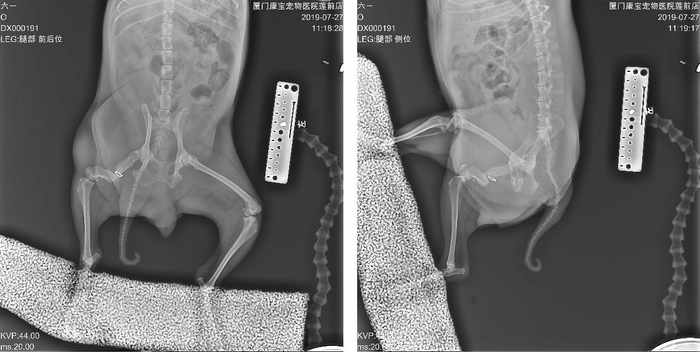

右后肢前外侧开口,先深部取样,并取出断端环扎钢丝并与深部样本一起送检细菌培养及药敏。彻底冲洗化脓疮,修整骨骼断端并重新打通骨髓腔,解剖复位骨折断端后,用银离子抗菌骨板固定。

因考虑到恢复期长,才有外侧及前侧双板固定的方式,并从同侧肱骨及髂骨翼移植大量骨松质在骨折断端,最大程度的促进骨骼愈合。

后期的恢复还算顺利,伤口一期愈合,术后一周就开始用患肢点地了,之后每月复查。6个月后,可以观察到骨折断端基本愈合,能用患肢正常走路。